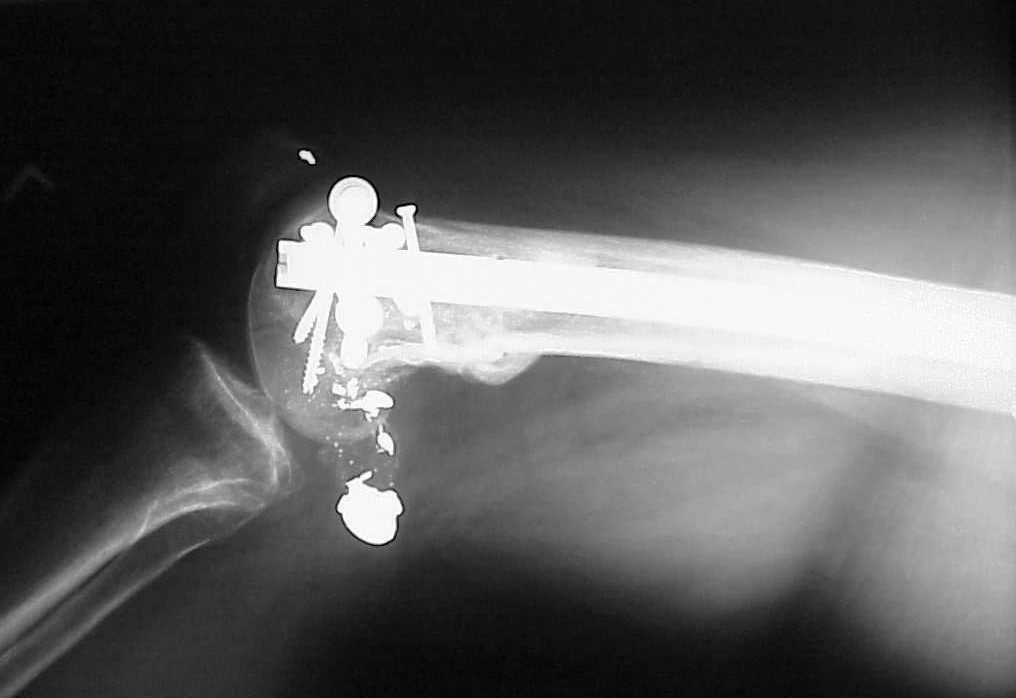

> How the screws should be placed?

Use 6.5 mm cannulated screws if you have and

place one anterior to where IMN will go if anterior cortex if insufficient and AP screws on either side of the IMN out of the trochlea to provide some additional varus/valgus stability. I worry about the leg going into valgus w/the lack of lateral cortex.

See attached case that was done several years ago before LISS. He had comminuted trochlea and anterior blocking screws were used to prevent anterior IMN cut-out.